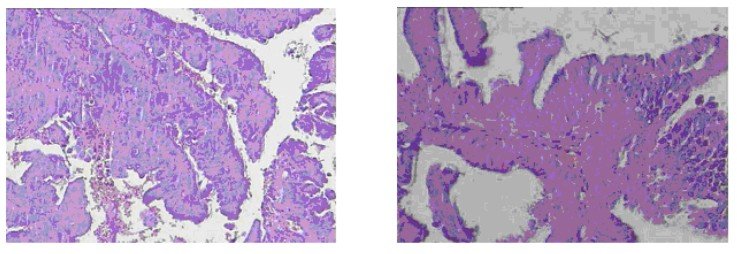

子宫内膜腺癌与 子宫内膜高分化乳头状腺癌

同张玻片,2个地方病理会诊,A给出的结果是“子宫内膜高分化乳头状腺癌",B给出的是"子宫内膜腺癌,伴坏死”,这两个意思是一样吗?哪个描述的更具体点?.求专家指点